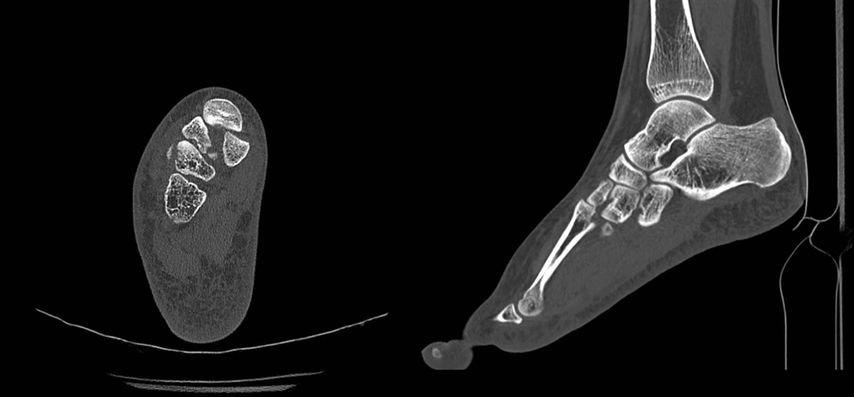

Die bildgebende Abklärung hat anfänglich durch nativradiologische Aufnahmen in seitlicher Projektion des gesamten Fußes, möglichst unter Belastung, sowie durch eine 45°-Schrägaufnahme des Mittelfußes und eine dorsoplantare Aufnahme mit 20°–30° nach kaudal gekippter Röhre zu erfolgen (Abb. 1).

Abb. 1: Bild einer möglichen Diastase zwischen der Basis des metatarsalen Gelenks II und des Os cuneiforme mediale, mögliche Ruptur des „Lisfranc-Ligaments“

Häufig findet sich in der nativradiologischen Bildgebung kein absolut sicherer Hinweis auf eine Fraktur oder Luxation, da sich die knöchernen Strukturen in der Projektion überlagern. Hier sind entweder gehaltene Röntgenaufnahmen unter Bildwandler oder eine computertomografische Abklärung durchzuführen (Abb. 2).

Abb. 2: CT-verifizierte knöcherne Absprengungen und Subluxation zwischen dem Os cuneiforme mediale und dem metatarsalen Gelenk II des in Abbildung 1 im Nativröntgen dargestellten Fußes